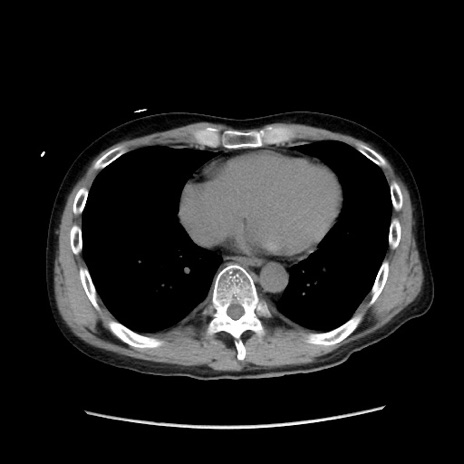

冠状断像